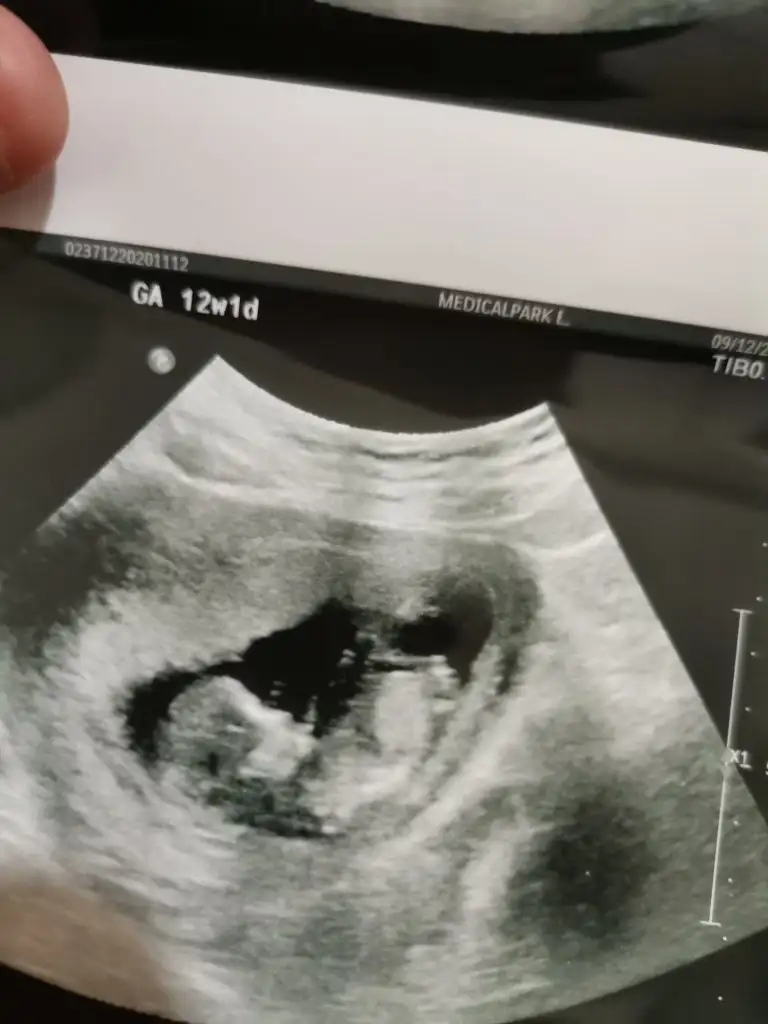

• IMG_20201213_203157.webp

IMG_20201213_203157.webp

35,5 KB · Görüntüleme: 75